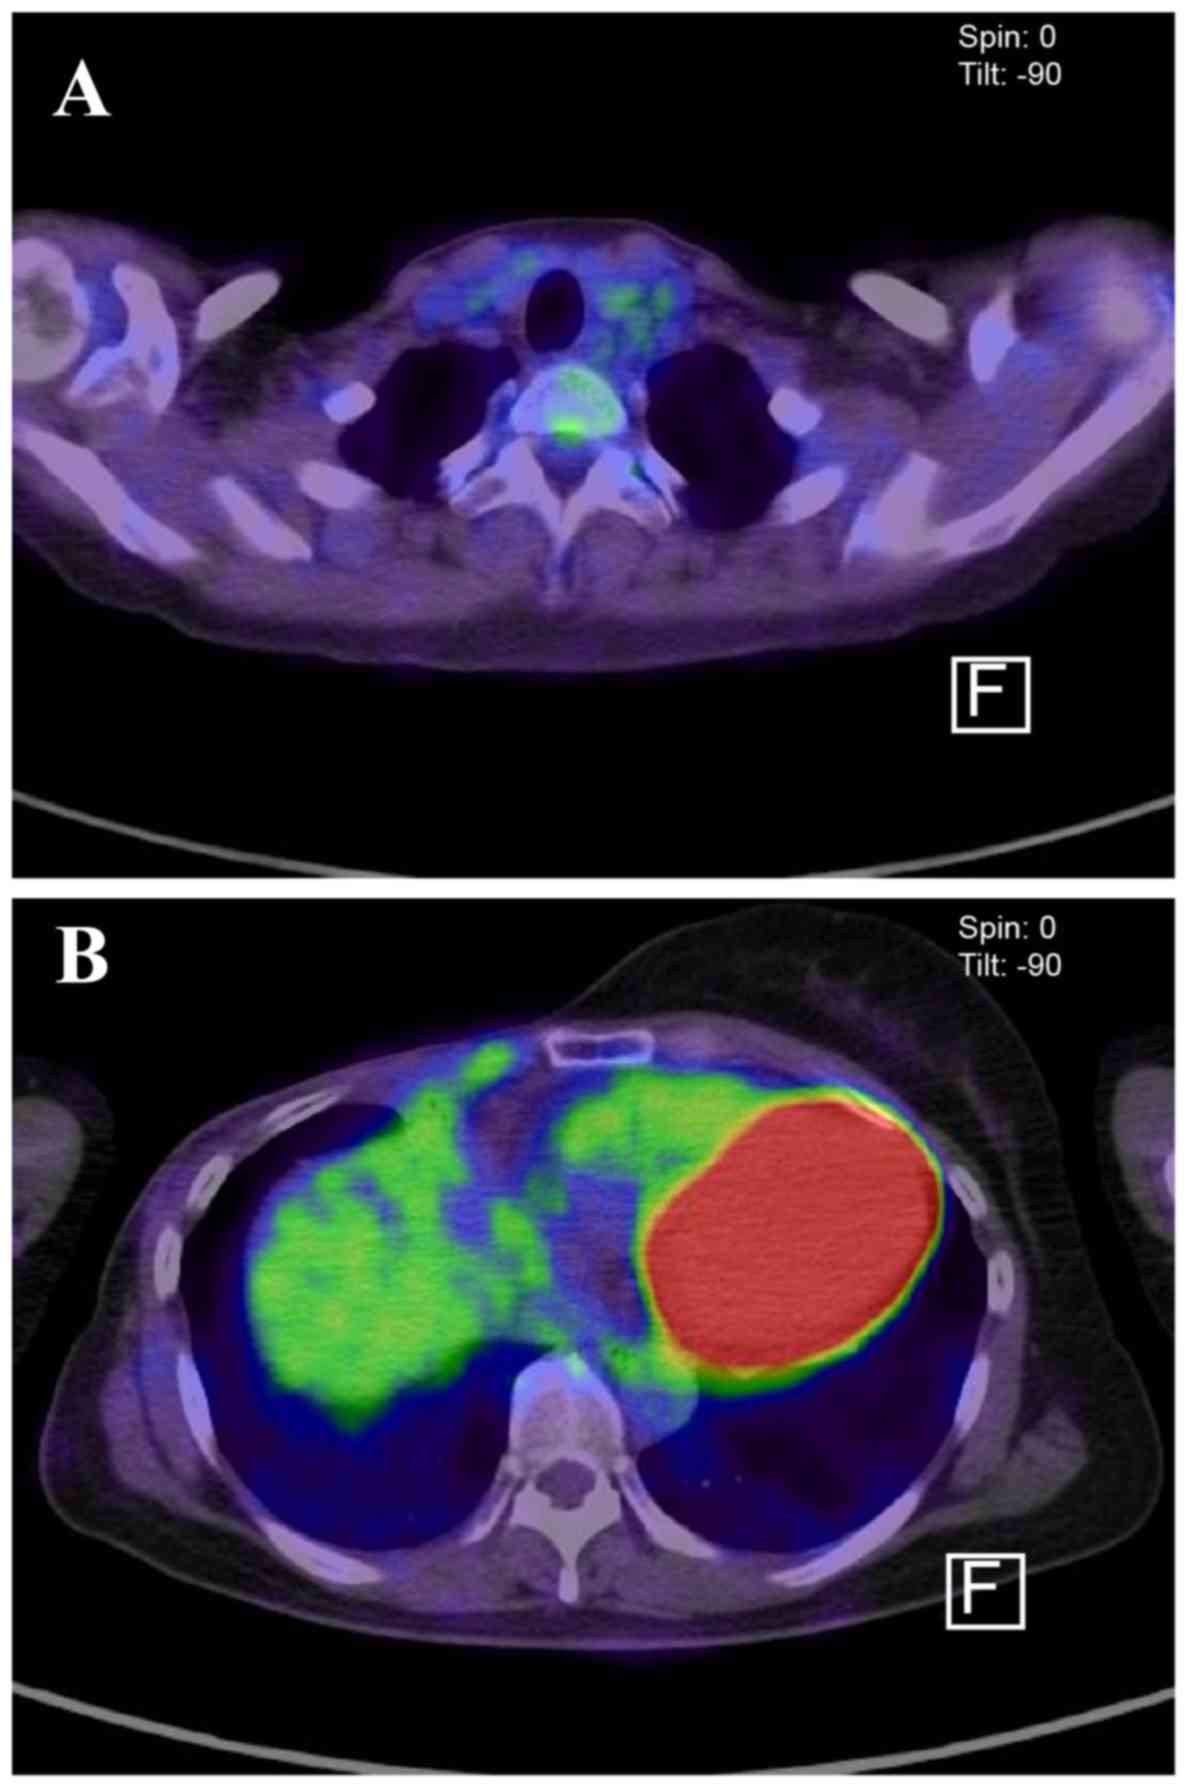

Figure 3.

Accumulation of fluorodeoxyglucose in (A) a supraclavicular lymph node and (B) the anterior thorax near the previous surgical site were confirmed by positron emission tomography-computed tomography prior to the initiation of chemotherapy.